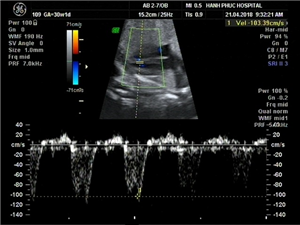

CLS: Siêu âm tim thai thông liên thất